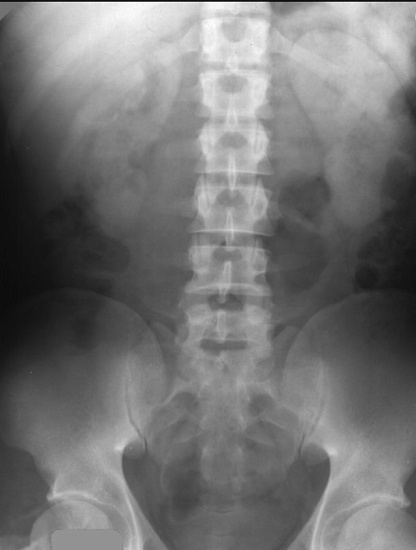

Рентгенография почек и мочевыводящих путей Рентгенография почек и мочевыводящих путей

Рентгенография почек и мочевыводящих путей

Рентгенография почек и мочевыводящих путей – важный метод визуализации почек, мочеточников и мочевого пузыря.

С помощью рентгенографии определяется положение почек, определяется наличие камней в мочевыделительной системе.